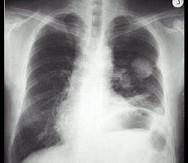

问题 男,67岁,胸痛半个月,胸片检查如图,最可能的诊断为 ( )

选项 A.左上肺结核球 B.左上肺周围型肺癌 C.左上肺炎性假瘤 D.左上肺球形不张 E.左上肺脓肿

答案 B